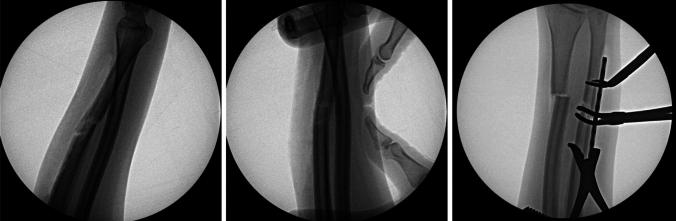

A 20-year-old pregnant female presented with an ulna fracture after a crush and bending type injury. Anatomic reduction of her ulna was not possible due to plastic deformation of the radius, requiring a corrective osteotomy of the radius. She is now 16 months out from surgery with full painless range of motion and radiographic union.

Plastic deformation of forearm fractures in adults is a rare phenomenon. It is possible that the patient's pregnancy contributed to her injury. Patients with uncommon fracture morphology can make operative intervention more complicated and necessitate additional procedures to achieve optimal motion and alignment.